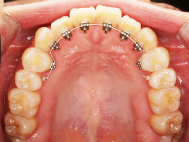

After

| 治療内容 | 上顎部分裏側矯正 下顎は目立ちにくい透明な装置 |

| 治療期間 | 11ヶ月 |

| 費用 | 620,000円 ※最新の治療費についてはご確認ください |

左上の前歯内側に入っている下の前歯ガチャ歯

左上前歯が下の歯の内側に入っているのが気になるとの事で来院されました。目立たない矯正治療を希望しているとのこでした。 上顎の装置は、歯の裏側(リンガル装置)で下顎は表側で矯正治療を行いました。口を閉じた時、上の前歯が内側に入っている為に下の歯を前に押し出している状態でした。その為、上の歯を前に出すだけではその歯が下とのかみ合わせの関係で、前に飛び出すような治療となってしまいます。 今回の症例ではシュミレーションを見て頂き、下の歯も治療し、内側へ下げることによって上の歯も飛びだすことなく、キレイにおさまることを説明し、上下一緒に矯正することをお勧めさせて頂きました。